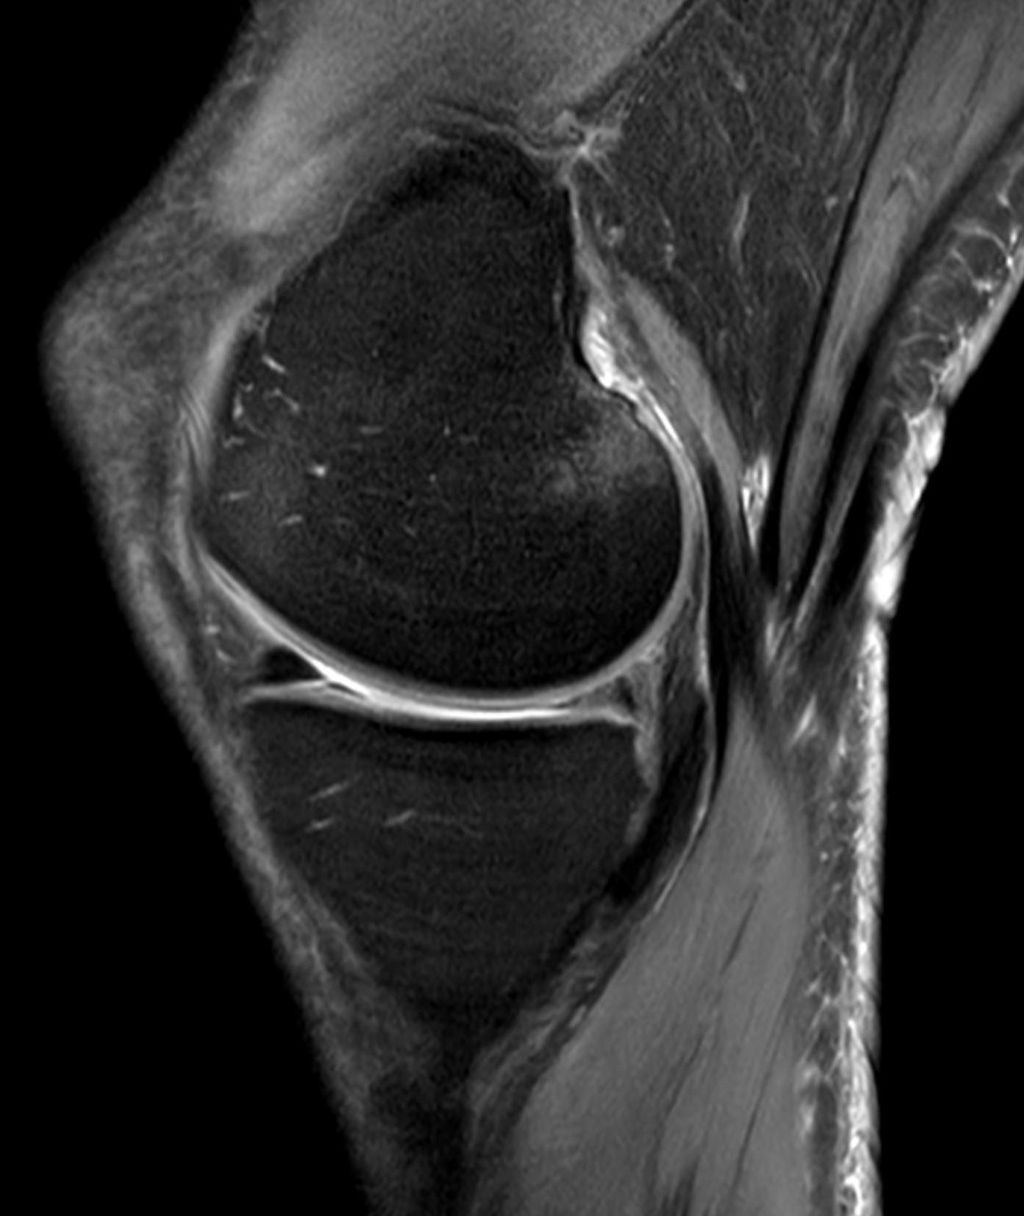

Diagnostic Tools and Techniques

Diagnostic tools and techniques for knee injuries and disorders include X-rays, MRI scans, and physical examinations. Patient assessments are also important in determining the extent of the injury or disorder and developing an appropriate treatment plan.